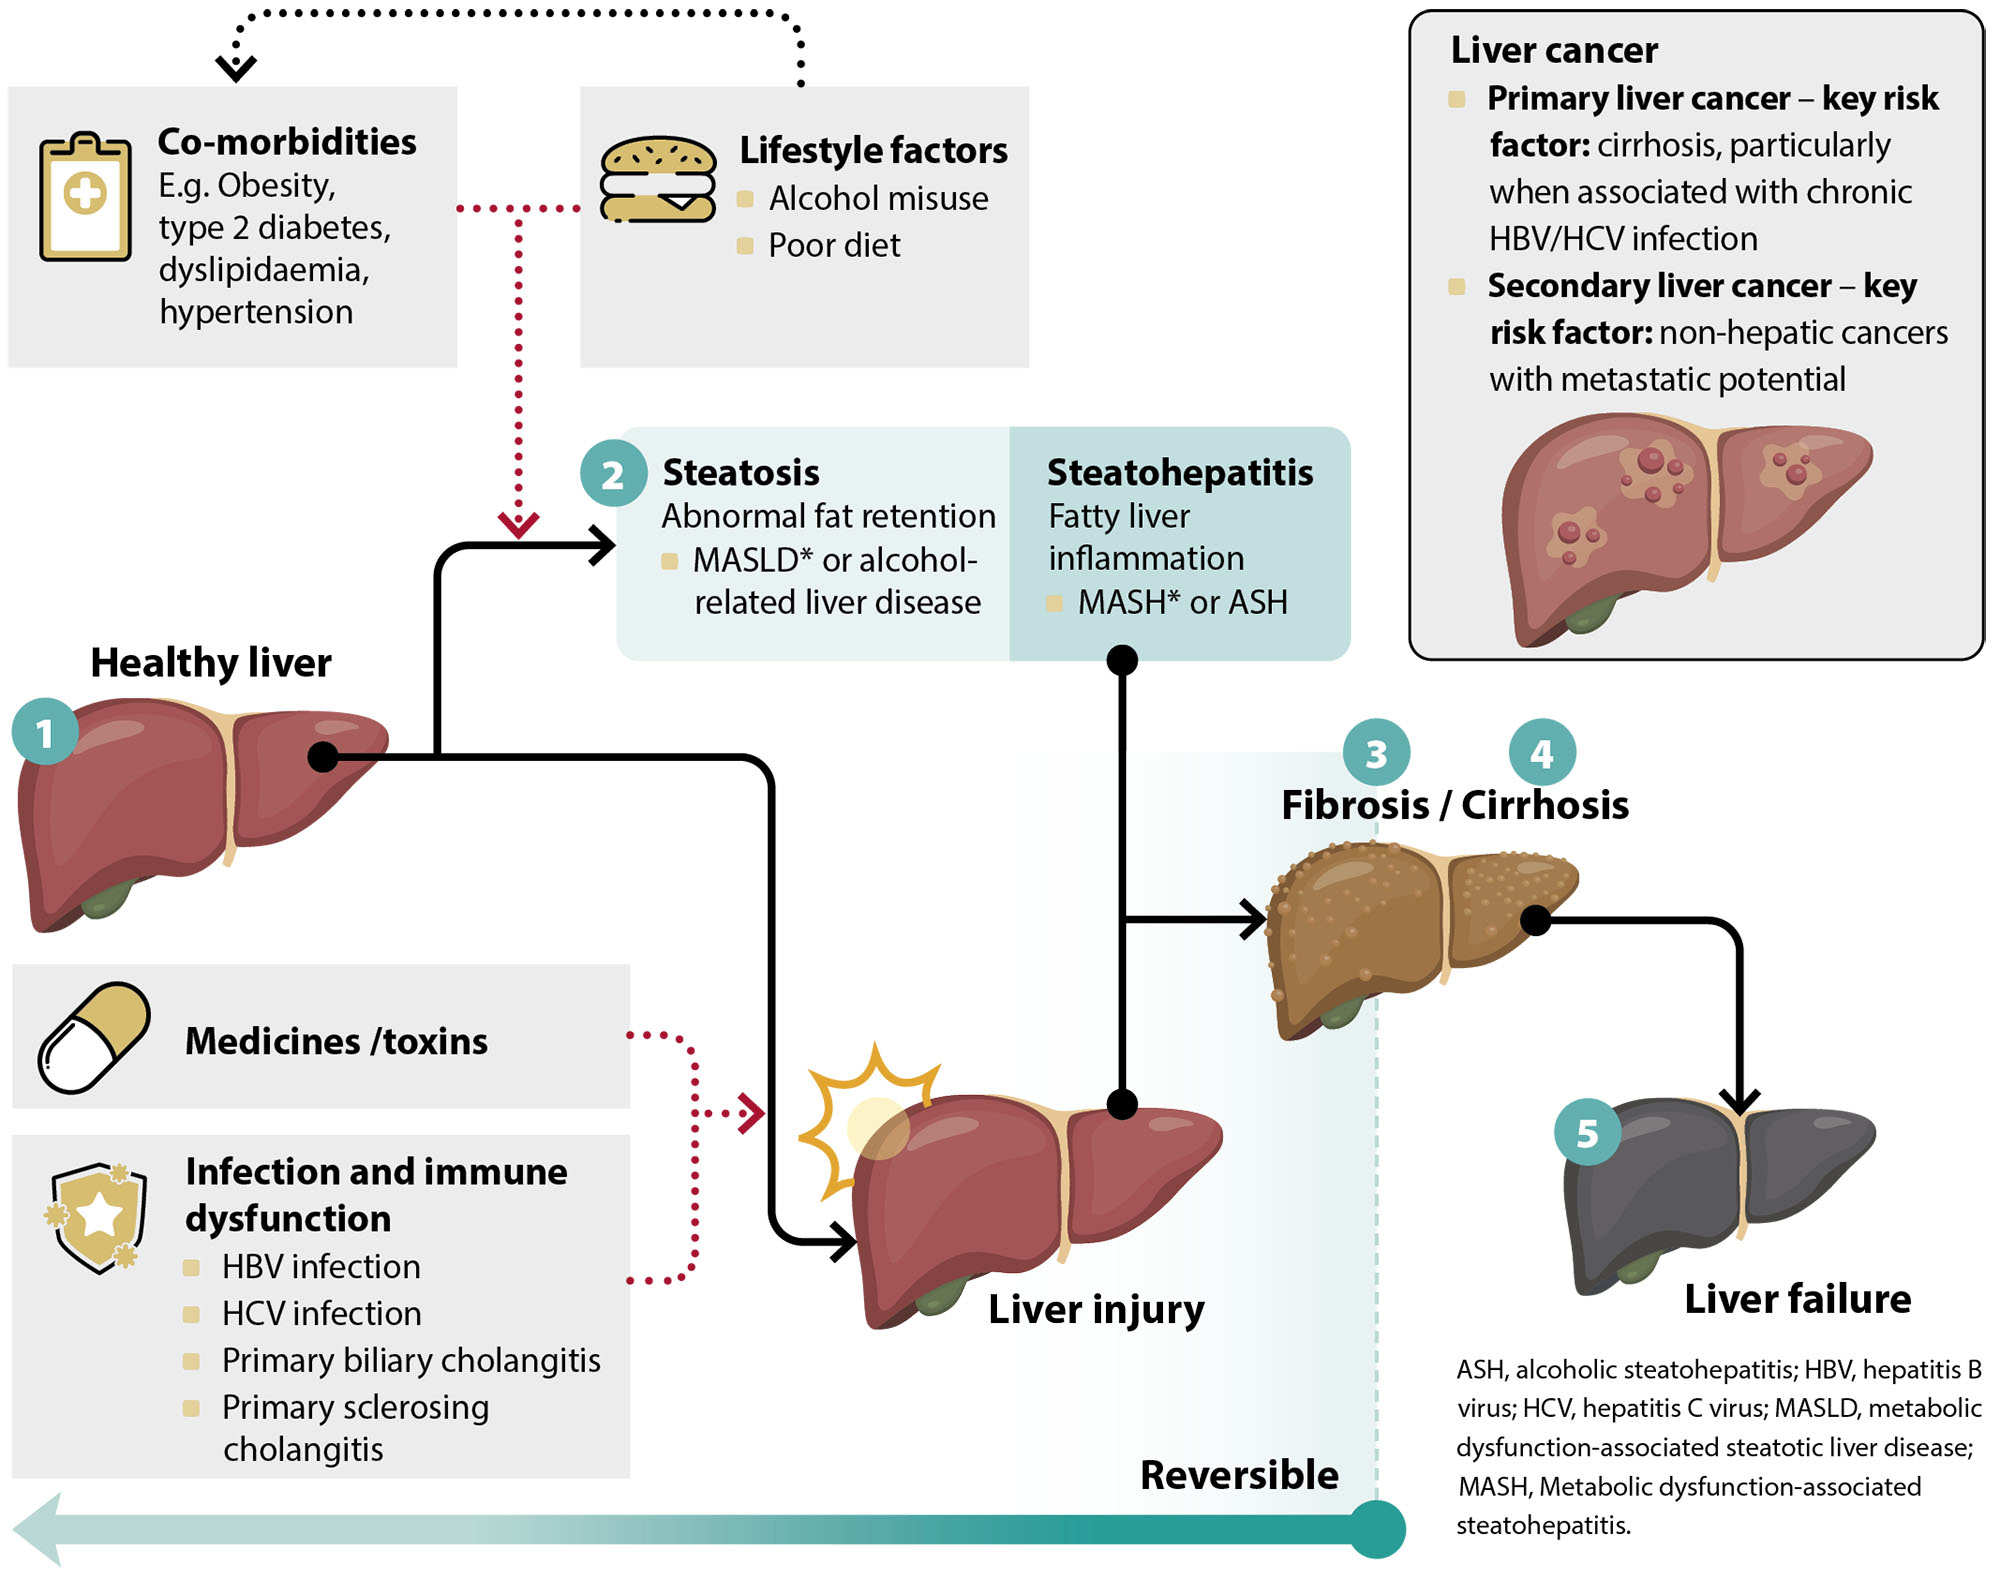

Direct Acting Antivirals Improve HCC Free Survival Liver Function In

How To Improve Liver Function With Cirrhosis A Holistic Approach

Biomedicines Free Full Text An Overview Of Hepatocellular Carcinoma

Can Liver Damage Be Reversed Liver Foundation

Cirrhosis Of The Liver Symptoms Diagnosis Survival Rate And Treatment

Hepatic Steatosis What Is It Causes Diagnosis Treatment And More